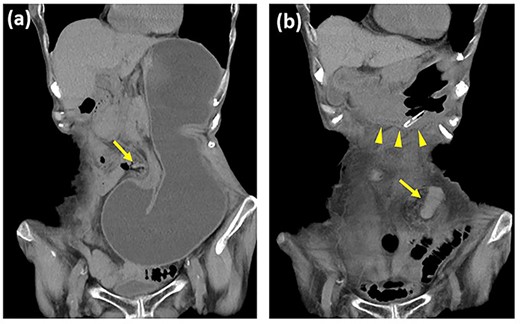

A laparoscopic operation was performed for the recurrent hernia. Intraoperative findings showed that the gastric hernia had been reduced and ischemic changes were not evident in the stomach (Fig. 2a). Because the lateral defect of the lifted sigmoid colostomy was too large for suturing closure, a new colostomy was constructed laparoscopically through an extraperitoneal route (Fig. 2b). The patient’s postoperative course was uncomplicated, and she had no recurrence of hernia within the 20 months of follow-up after the surgery.

Intraoperative findings of hernia repair. (a) The gastric incarceration is not evident in the lateral space of the sigmoid colostomy (arrow) at the time of exploration. (b) The colostomy is reestablished through an extraperitoneal route using the same stoma site.